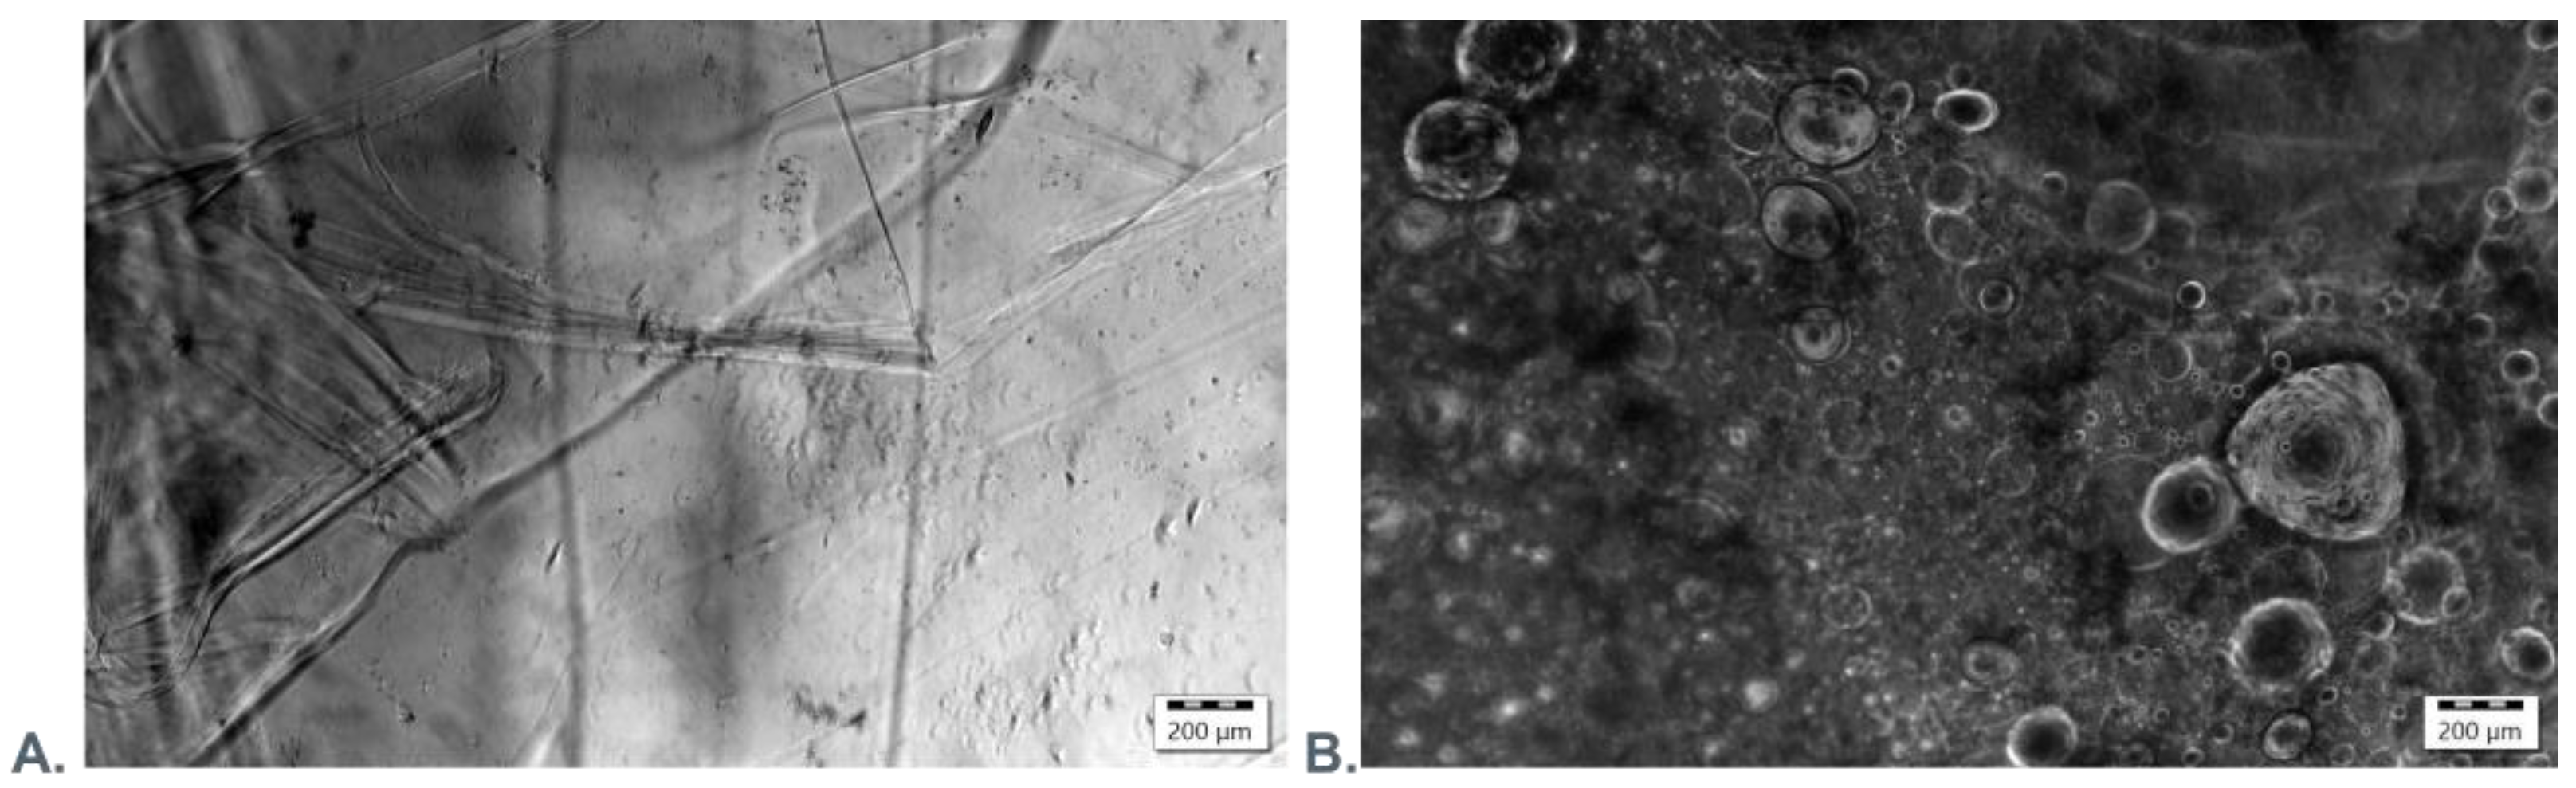

3.3. Microscopic Evaluation of Morphology of Coating and Oxygenating Elements Presence